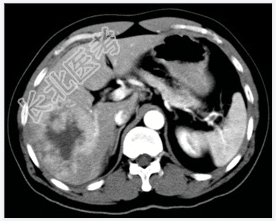

- [材料题] 患者,男性,52岁,因右上腹痛1个月、加重3天入院。体查:肝不大,肝区触痛明显,脾不大。实验室检查血AFP明显增高。行上腹部CT平扫+增强扫描。

- 简答题1、患者的诊断及依据是什么?

- 简答题2、鉴别诊断有哪些?